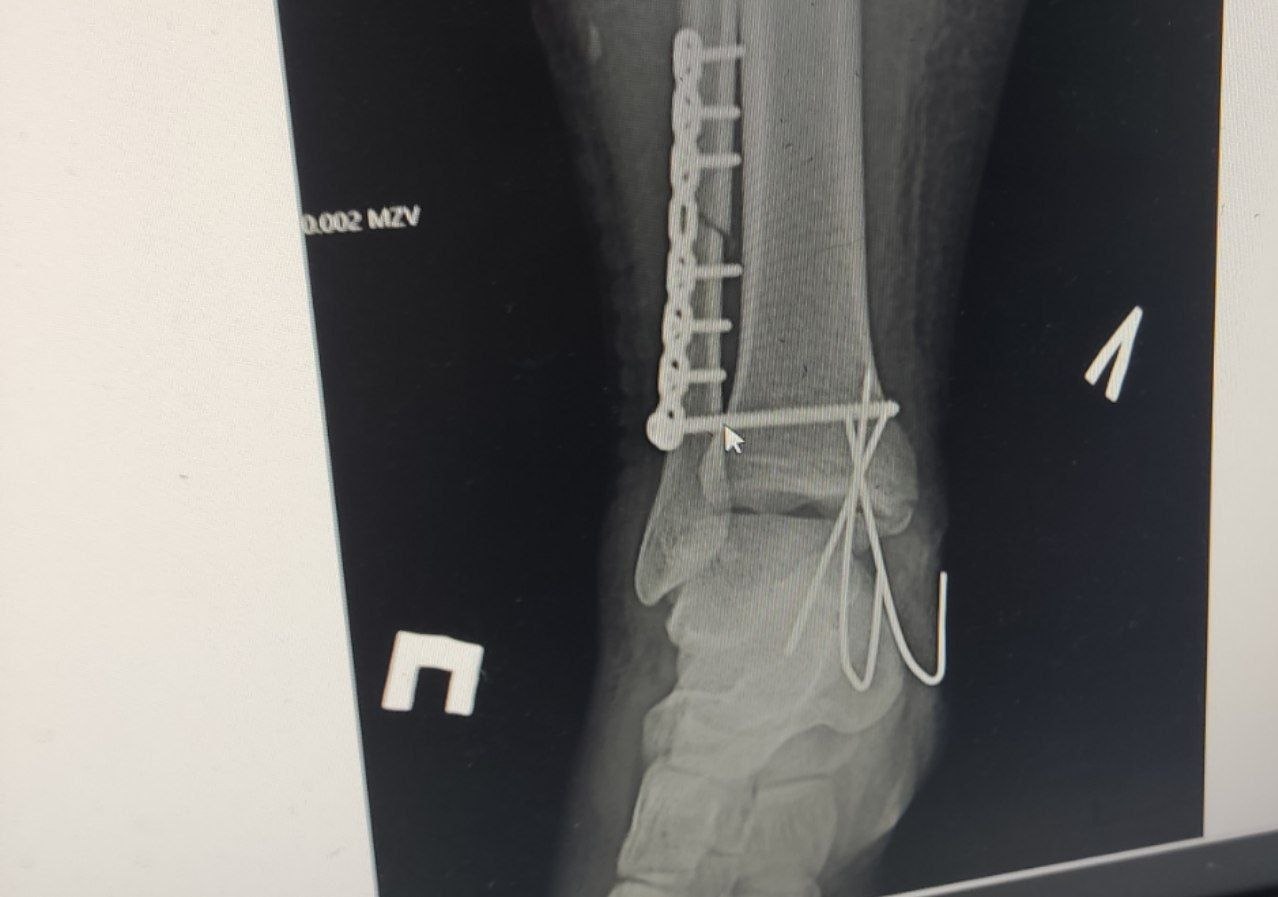

Медицинские документы фиксируют вред здоровью, который получил мальчик: «полный поперечный перелом нижней трети диафиза малоберцовой кости со смещением, полный оскольчатый внутрисуставной перелом внутренней лодыжки большеберцовой кости, разрыв дистального межберцового синдесмоза, подвывих стопы» — простыми словами: нога подростка была раздроблена, кости сместились, связки порваны, сустав вывихнут.

В день травмы мальчику сделали закрытую репозицию — кости вправили без разреза. Через три дня ногу разрезали, поставили пластину и винты. Спустя несколько месяцев металлоконструкцию удалили, но сустав за это время разрушился. Поэтому Кириллу потребовалась ещё одна операция. Семья поехала в федеральный центр детской травматологии и ортопедии в Санкт-Петербург, там кость пришлось ломать и сращивать заново.

Кириллу пришлось сломать уже сросшуюся кость, чтобы срастить её заново

Снимок ноги Кирилла, где видно какая кость сломана